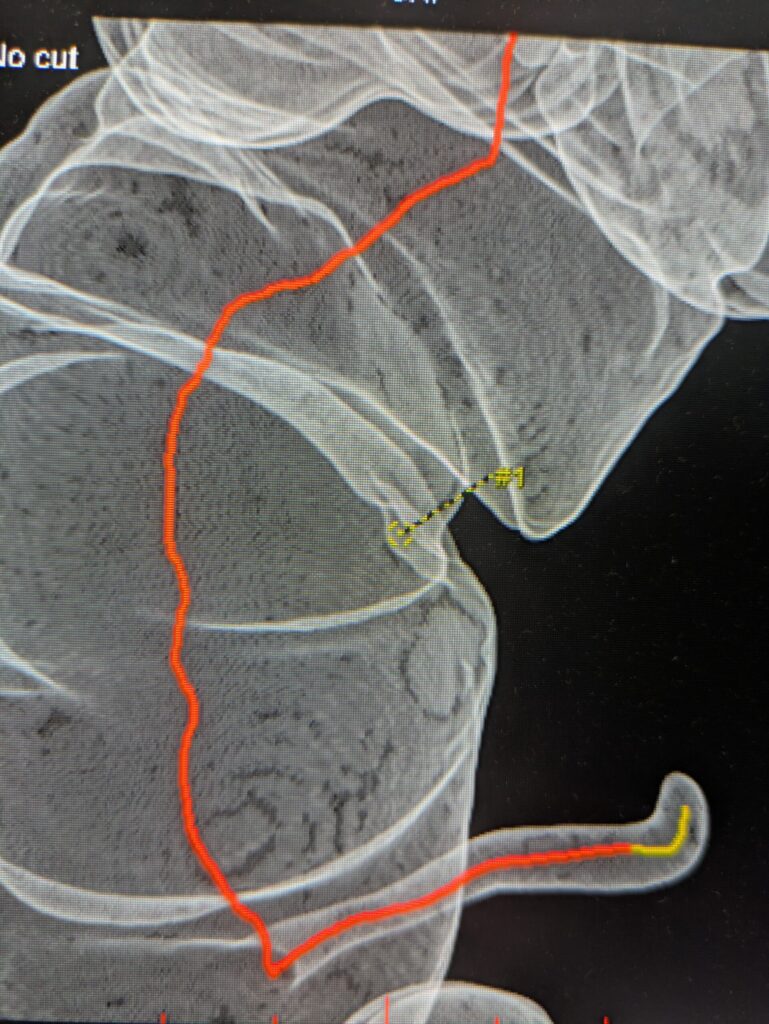

CTC uses CT scanning to create 3D images of the colon, allowing doctors to “virtually” inspect the inside without inserting a scope.

4. 3D images and maps are generated with software.

Tagging Method

• Small amounts of barium or iodine solution are ingested.

• Residual stool/liquid becomes “tagged” (bright) on CT.

• Doctors can distinguish stool from polyps.

• Software can even digitally remove tagged stool.